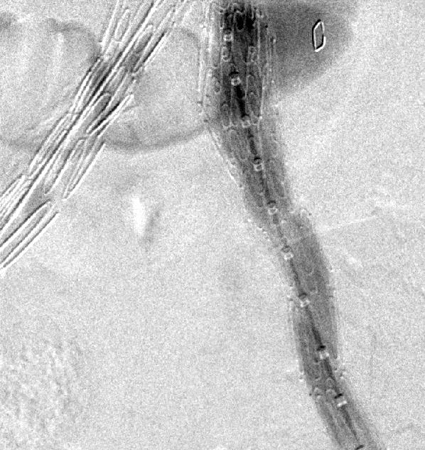

Debe hacerse todo lo posible para reparar la fuga interna de tipo I antes de completar el procedimiento (p. ej., moldeado con balón de la zona de sellado proximal, colocación de un manguito proximal, endostaples, embolización líquida).[248] Para los pacientes con un sellado proximal comprometido después de la reparación endovascular del aneurisma aórtico abdominal, se debe considerar la extensión proximal con dispositivos fenestrados y ramificados.[2] La endofuga persistente de tipo IA puede requerir la conversión a reparación abierta, siempre que el riesgo quirúrgico sea aceptable.[2][77][249][Figure caption and citation for the preceding image starts]: Extensión de endoprótesis expandida para la misma endofuga tipo I (marcada con un círculo)University of Michigan, específicamente los casos del Dr. Upchurch que reflejan los Departamentos de Cirugía Vascular y Radiología [Citation ends].